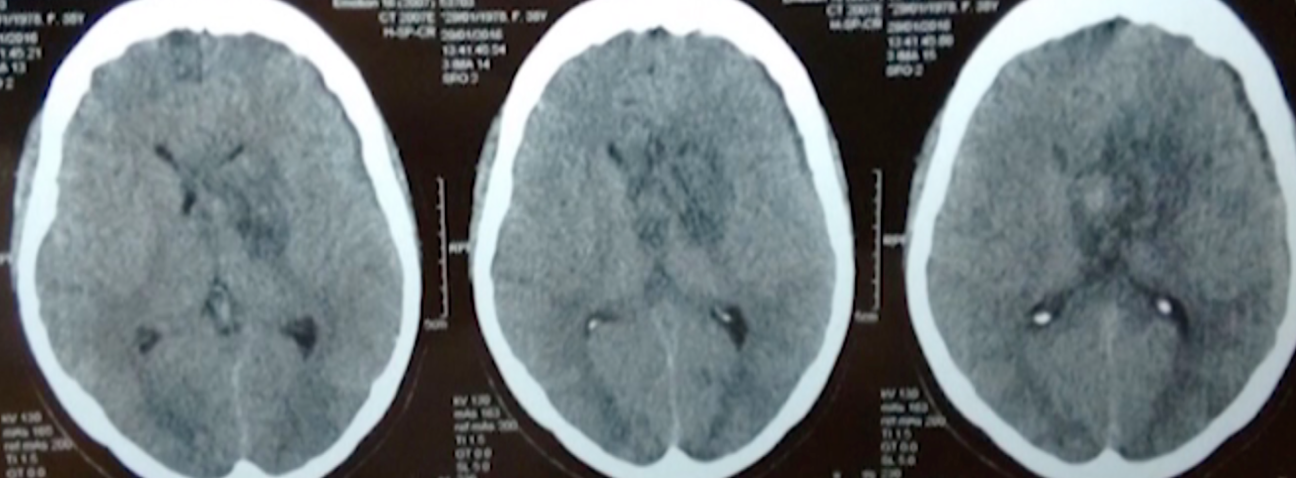

La cirugía consistió en un abordaje interhemisférico transcalloso anterior. Inmediatamente después de la callosotomía se observó a nivel intraventricular un abundante coágulo sanguíneo con presencia de áreas sólidas. Luego de evacuado el hematoma se visualizó una cápsula de color verdoso, la cual fue también resecada completamente (Figura 2). No se realizó biopsia por congelación; en su lugar se llevó a cabo una exéresis macroscópica completa de la lesión y se enviaron fragmentos del hematoma evacuado y de la cápsula resecada para análisis anatomopatológico por diferido.

Figura 2: Imágenes intraoperatorias de la exéresis de la lesión. A: callosotomía luego de la cual se evidenció el coágulo sanguíneo. B: Exéresis del cavernoma de a porciones desde el interior de la lesión C: Se evacuó el hematoma en su totalidad y posteriormente se observó la cápsula verdosa la cual también fue resecada. Ant: anterior, Lat: lateral, Post: posterior, CC: cuerpo calloso, HC: hoz del cerebro, H: hematoma, Cap: cápsula.